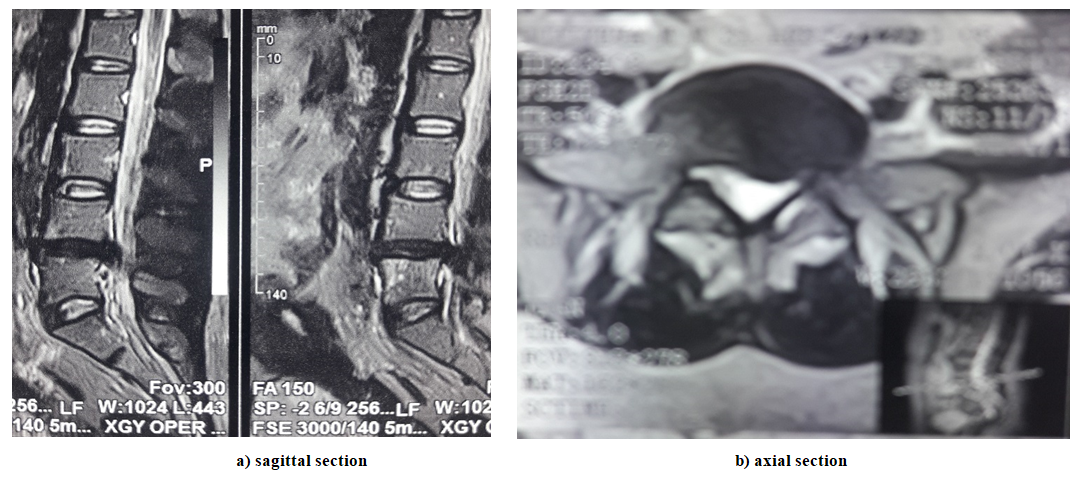

All patients who were admitted urgently had their neurological status assessed and MSCT performed./MRI of the lumbosacral spine to clarify the level, localization and nature of the pathological process (the level and localization of intervertebral disc involvement in the pathological process, the location of the intervertebral disc herniation across the spinal canal (median, paramedian, posterolateral or foraminal), the degree of herniation (elastic protrusion, sequestered prolapse). | Figure 2. MRI of a dislodged sequestered herniated intervertebral disc with migration of the fragment downwards at the vL4-L5 level |

| Figure 3. MRI of a dislodged sequestered herniated intervertebral disc with migration of the fragment downwards at the vL5-S1 level |